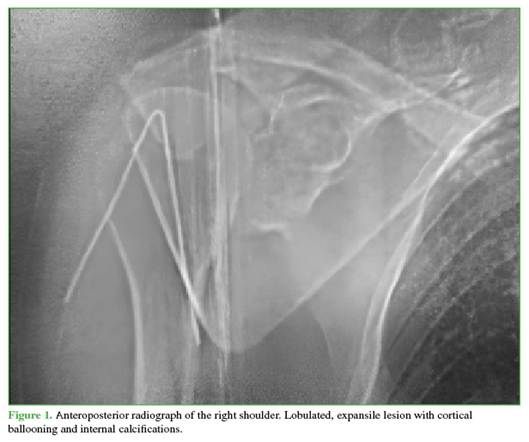

A 47-year-old man presented with right shoulder pain of one year’s duration. Physical examination revealed pain and functional limitation with restriction of all ranges of shoulder motion. Shoulder radiographs, computed tomography (CT), and magnetic resonance imaging (MRI) were obtained. Imaging showed a lobulated, expansile lesion with cortical ballooning and internal calcifications (Figure 1). On sagittal CT slices, hypodense areas were visible within the glenoid, and on T2-weighted MRI there was hyperintensity in the supraspinous fossa involving the infraspinatus and subscapularis muscles (Figure 2).